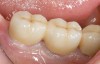

Figure 3  Removable prostheses can provide proper support and enhance overall facial esthetics for the patient.

Figure 3